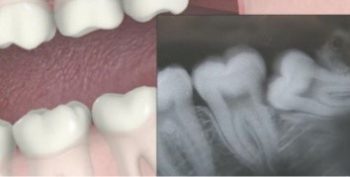

ฟันคุด คืออะไร?

ฟันคุด เป็นฟันกรามซี่สุดท้ายที่ไม่สามารถขึ้นในช่องปากได้อย่างปกติ มักอาจทำให้เกิดอาการปวดและนำไปสู่การติดเชื้อได้ ส่วนใหญ่ทันตแพทย์จะแนะนำให้ผ่าฟันคุดออก

1. X-ray ตรวจเช็คตำแหน่งและลักษณะของฟันคุด